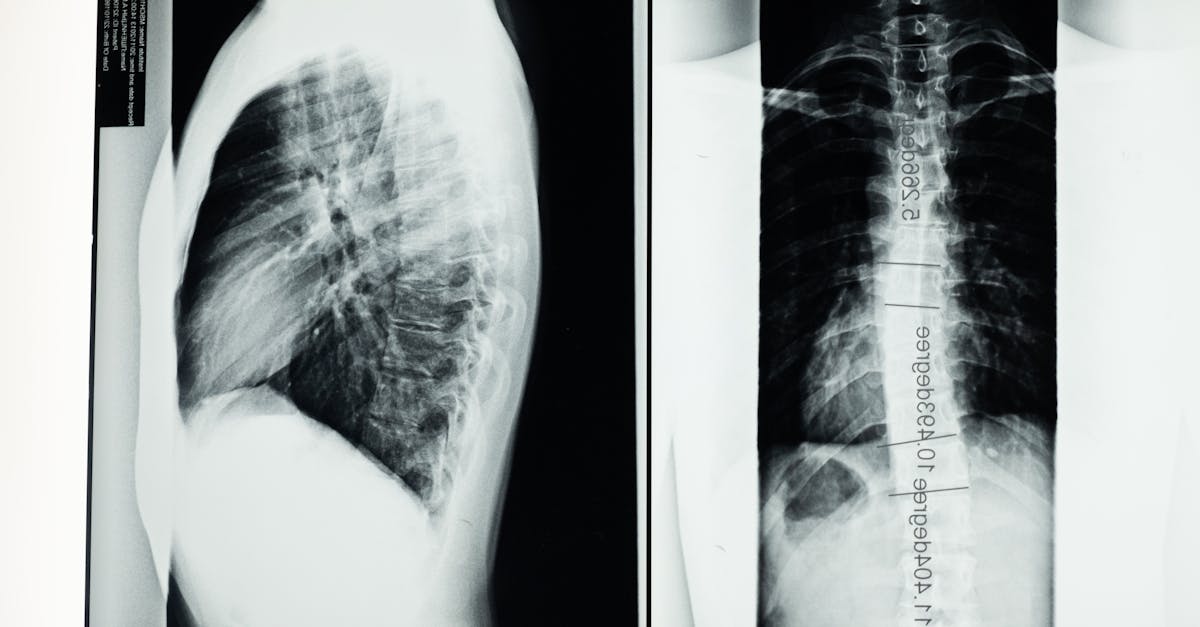

Dans certains cas, des examens complémentaires sont nécessaires pour affiner le diagnostic. Cela peut inclure des radiographies, des IRM ou des scanners pour visualiser les structures internes de la colonne vertébrale. Ces examens aident à identifier des conditions spécifiques comme des hernies discales ou des sténoses, qui peuvent nécessiter un traitement par décompression neurovertébrale. Il est important de sélectionner les examens appropriés en fonction des résultats de l’anamnèse et de l’examen physique.

- Examens complémentaires: Utilisation d’imageries comme IRM ou radiographies si nécessaire.

- Imageries médicales : IRM, radiographies ou scanners pour visualiser les anomalies.

| Examens complémentaires | Réalisation de tests diagnostiques (IRM, radiographies) pour affiner le diagnostic. |

Dans certains cas, pour corroborer les hypothèses formulées durant l’examen physique, le médecin pourra ordonner des examens complémentaires. Ces examens peuvent inclure des imageries telles que des IRM ou des radiographies, ou encore des analyses sanguines. Ils sont essentiels pour valider le diagnostic et obtenir une image claire de l’état de la colonne vertébrale et des nerfs environnants. Chaque type d’examen vise à répondre à une question clinique précise. Il peut également révéler des maladies sous-jacentes qui nécessiteraient une attention particulière avant de procéder à tout traitement de décompression neurovertébrale.

Enfin, si nécessaire, des examens complémentaires peuvent être demandés. Ceux-ci, tel qu’une IRM ou un scanner, fournissent des détails supplémentaires sur la condition des structures vertébrales et du système nerveux. Ces examens sont une étape essentielle pour confirmer une hypothèse diagnostique et pour orienter le traitement par décompression neurovertébrale.